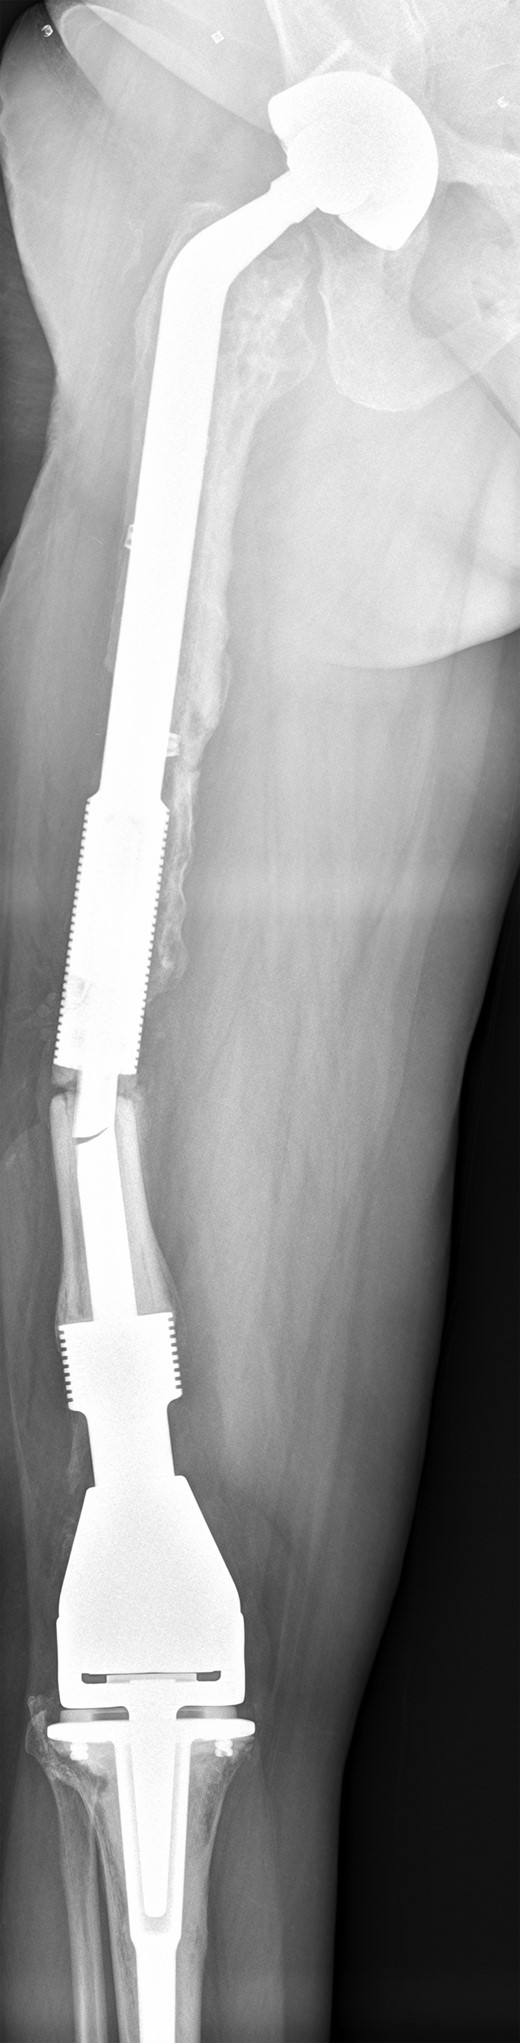

She subsequently sustained a periprosthetic fracture at the distal tip of her right total hip replacement (Fig. 1). An initial attempt was made to manage this fracture with a plate and Dall-Miles cables (Fig. 2); however, the fracture did not unite. The patient went on to have a custom-made cement-linked internal proximal femoral replacement, which had a hollow cylindrical design to accept the stem of the existing well-fixed distal femoral component (Figs 3 and 4). This linked prosthesis effectively converted her separate prostheses to a total femoral replacement, sparing her distal femoral replacement from revision. She had no problems postoperatively and recovered well from her surgery.

Custom-made cement-linked internal proximal femoral replacement.

Existing distal femoral replacement with stem linked to custom-made internal proximal femoral component visible in upper half of the image.